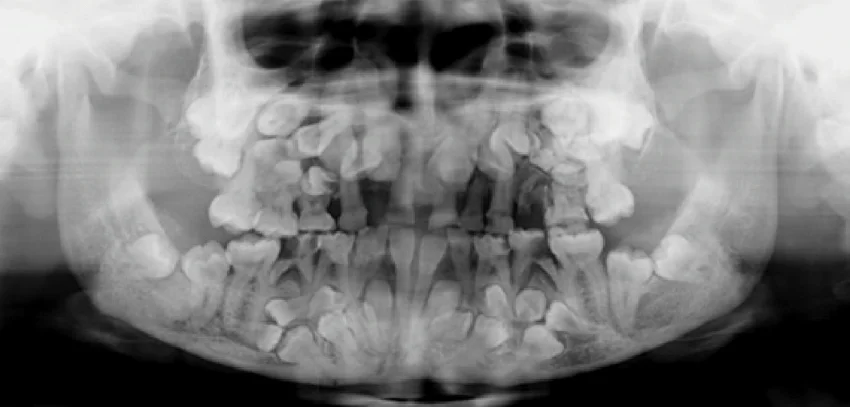

сколько зубов у человека - изображение 1